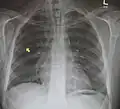

El diagnóstico puede confirmarse mediante una radiografía de tórax en la que aparezca un contorno radiolúcido alrededor del corazón y el mediastino o mediante un TAC de tórax.

Neumomediastino y neumotórax derecho tras fractura de la primera costilla en accidente de bicicleta de montaña. -